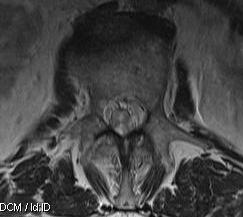

Ependymoma Conus MRI SagittalEpendymoma Conus Axial MRI